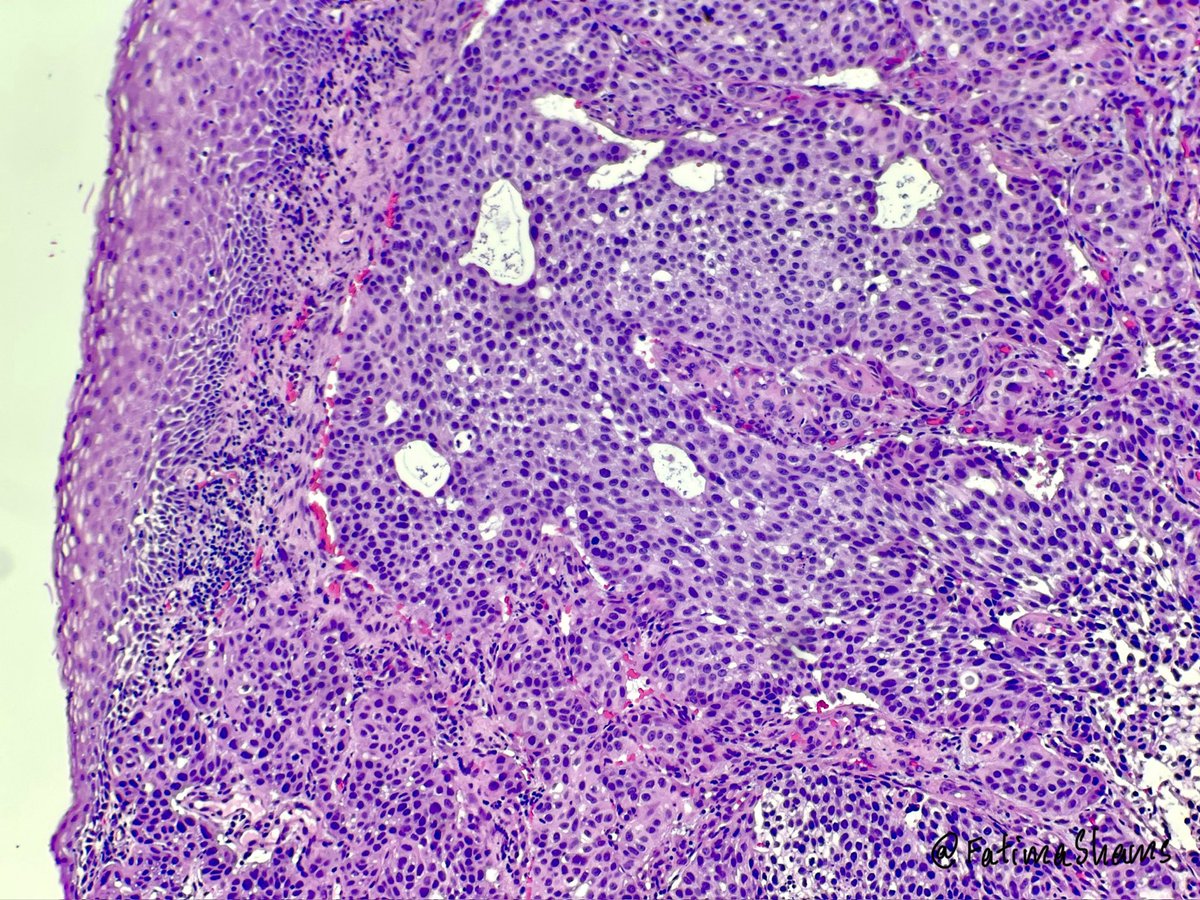

👉68YO female with prior cystectomy for urothelial carcinoma now presents with postmenopausal bleeding and a suspicious cervical mass. ⁉️ What is your diagnosis, and what additional work-up would you perform? #pathtwitter #gynepath #uropath #pathresidents #pathology #surgpath